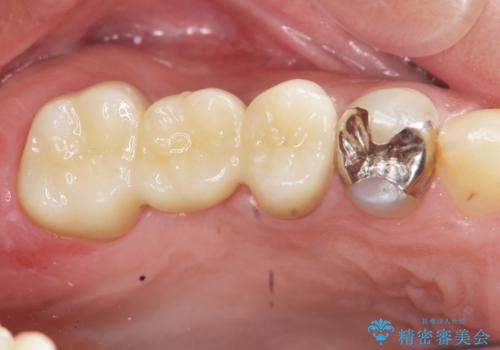

- 49.5万円 (フルジルコニアクラウン×5)費用は治療当時の料金となります

自然な仕上がりに、満足いただくことができました。

今後他の銀歯も外していく予定です。